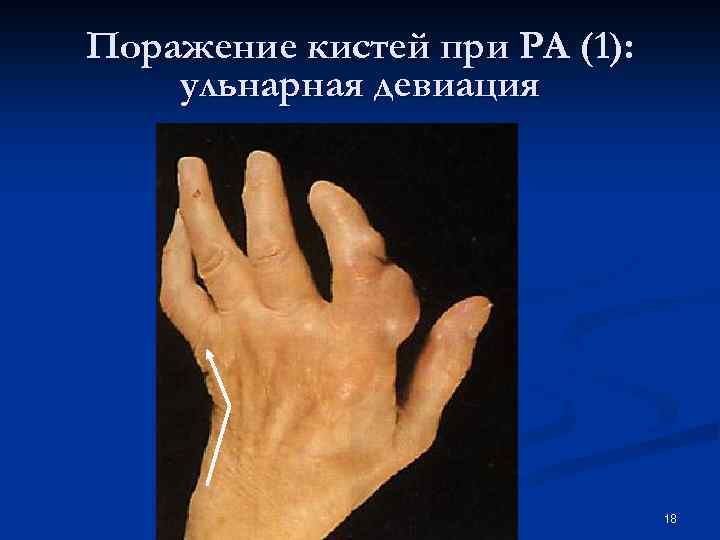

Поражение кистей при РА (1): ульнарная девиация 18

Поражение кистей при РА (1): ульнарная девиация 18